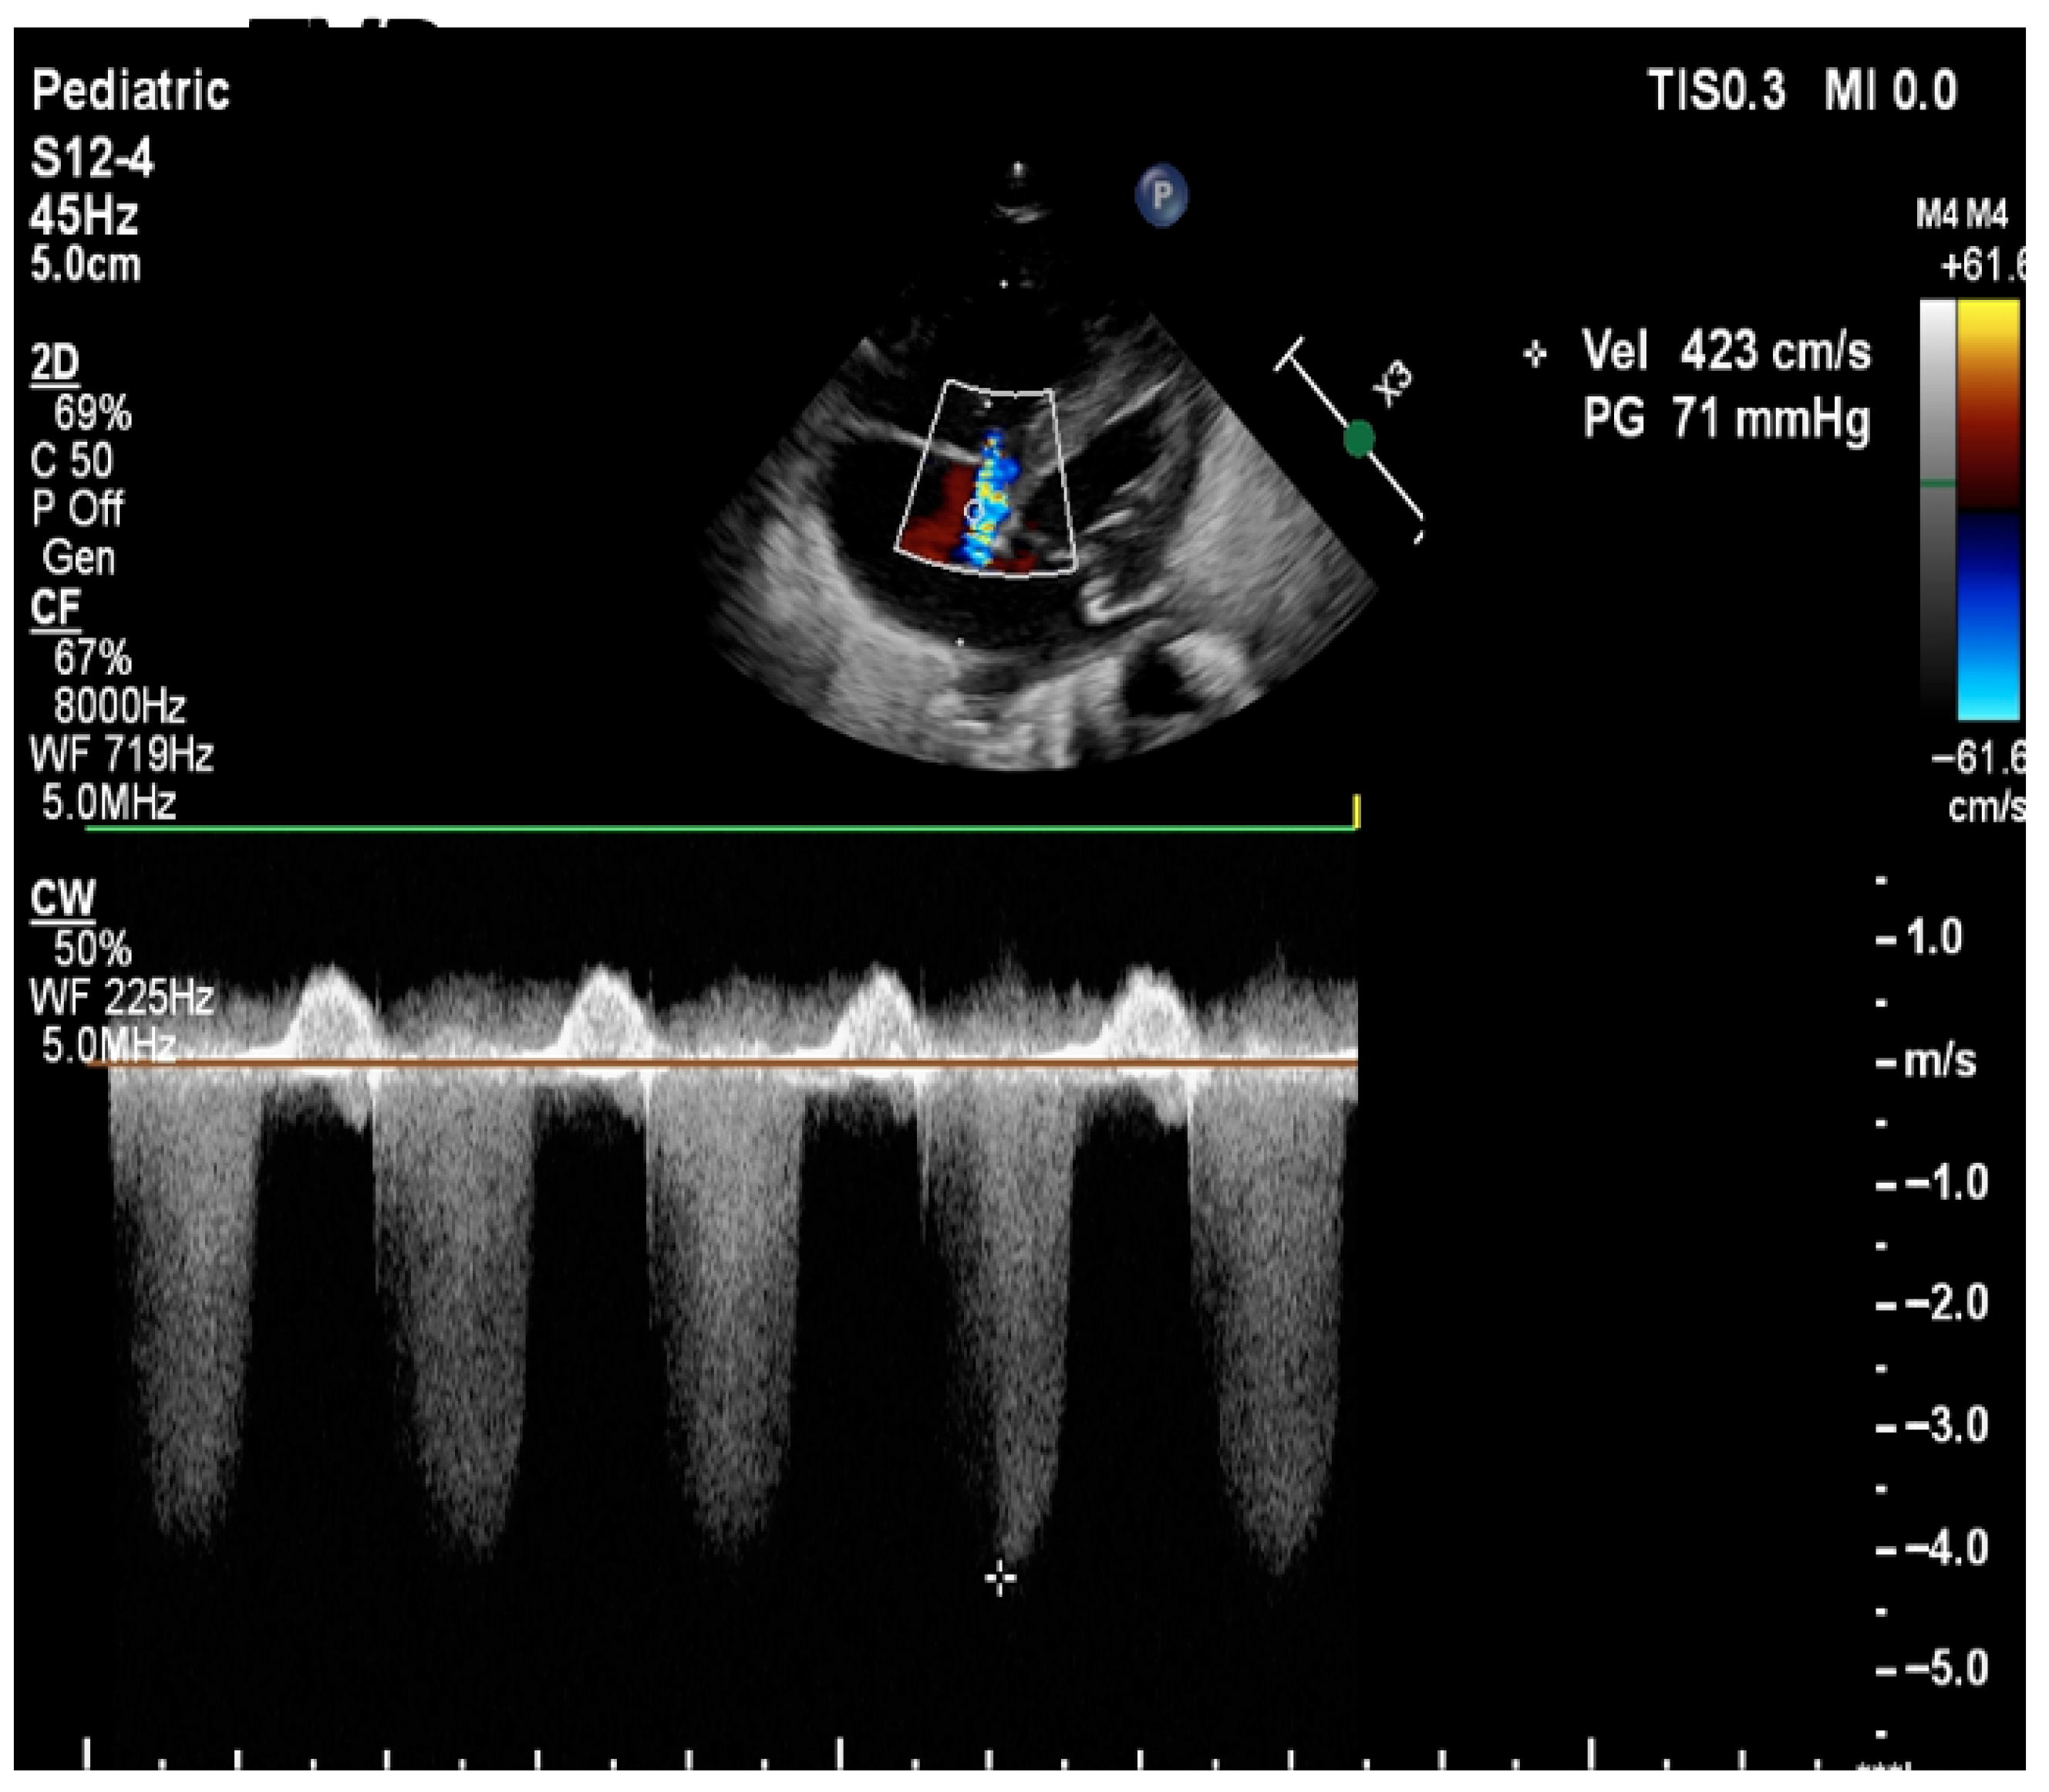

| Pulmonary Artery Pressure Measurement | Estimation based on the velocity of blood flow through regurgitant flow across the tricuspid valve using the Bernoulli equation | SPAP = 4 (TR Vmax2+ right atrial pressure (RAP) V: the velocity of regurgitation through the tricuspid valve RAP: the estimated right atrial pressure (3–10 mmHg). Pressures in the right ventricle and pulmonary artery are crucial for assessing the degree of pulmonary hypertension TV is present in approximately 60–85% of patients with PPHN. Absence of TR or minimal TR does not rule out PPHN! |

| Detection of Shunt | Identification and assessment of flow through the patent foramen ovale (PFO) and ductus arteriosus (PDA) | Indicates the presence and nature of pathological flow: left-to-right, bidirectional (often in moderate PPHN), or right-to-left (in very severe PPHN) |